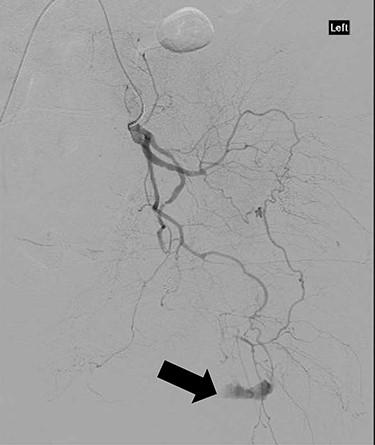

CT angiography showed multiple hypertrophied branches of the left internal iliac artery with heavy collateralisation to the territory of occluded left common femoral artery. Pathological dilatation of the collateral branch of the left obturator artery was identified as source of bleeding and embolized (Fig. 2). A further source of bleeding from a collateral muscular branch of the internal iliac artery was also embolized (Fig. 3).

CT angiography showing extravasation of dye from muscular branch of the internal iliac artery (black arrow).